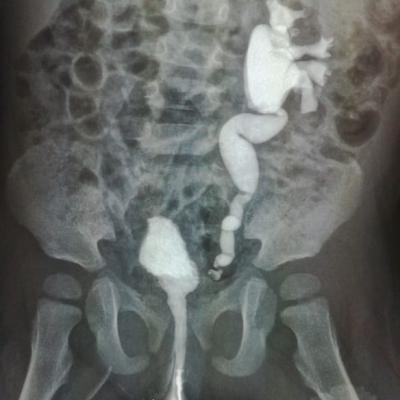

ПМР 4 степени

Здравствуйте.Моему ребенку 14.09.17г.р.была сделана вторая эндоскопическая коррекция ПМР 4 ст. в академии педиатрии СПб 07.06.19,(хотя рекомендовали и квоту одобрили на сложную операцию).08.06.19нас выписали.11.06.19г. ОАМ -удельный вес 1.006; лейкоциты 500(654,9); бактерии 13117,9;мочиться стала ещё реже 3 раза в день.17.06.19 были на приеме у нефролога,кот.нас направил обратно к урологам Академии педиатрии.Зав.отд.,посмотрев ОАМ и выписку ,спросил что я от него хочу...что ОАМ ещё ни о чем не говорит.Назначил прием Фурагина 3 раза в день по 50 мг в теч.месяца.А Вы как считаете,что лучше при такой степени рефлюкса,если почки уже страдают.